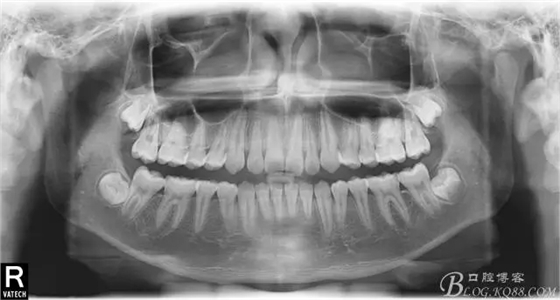

術(shù)后全景,側(cè)位照。